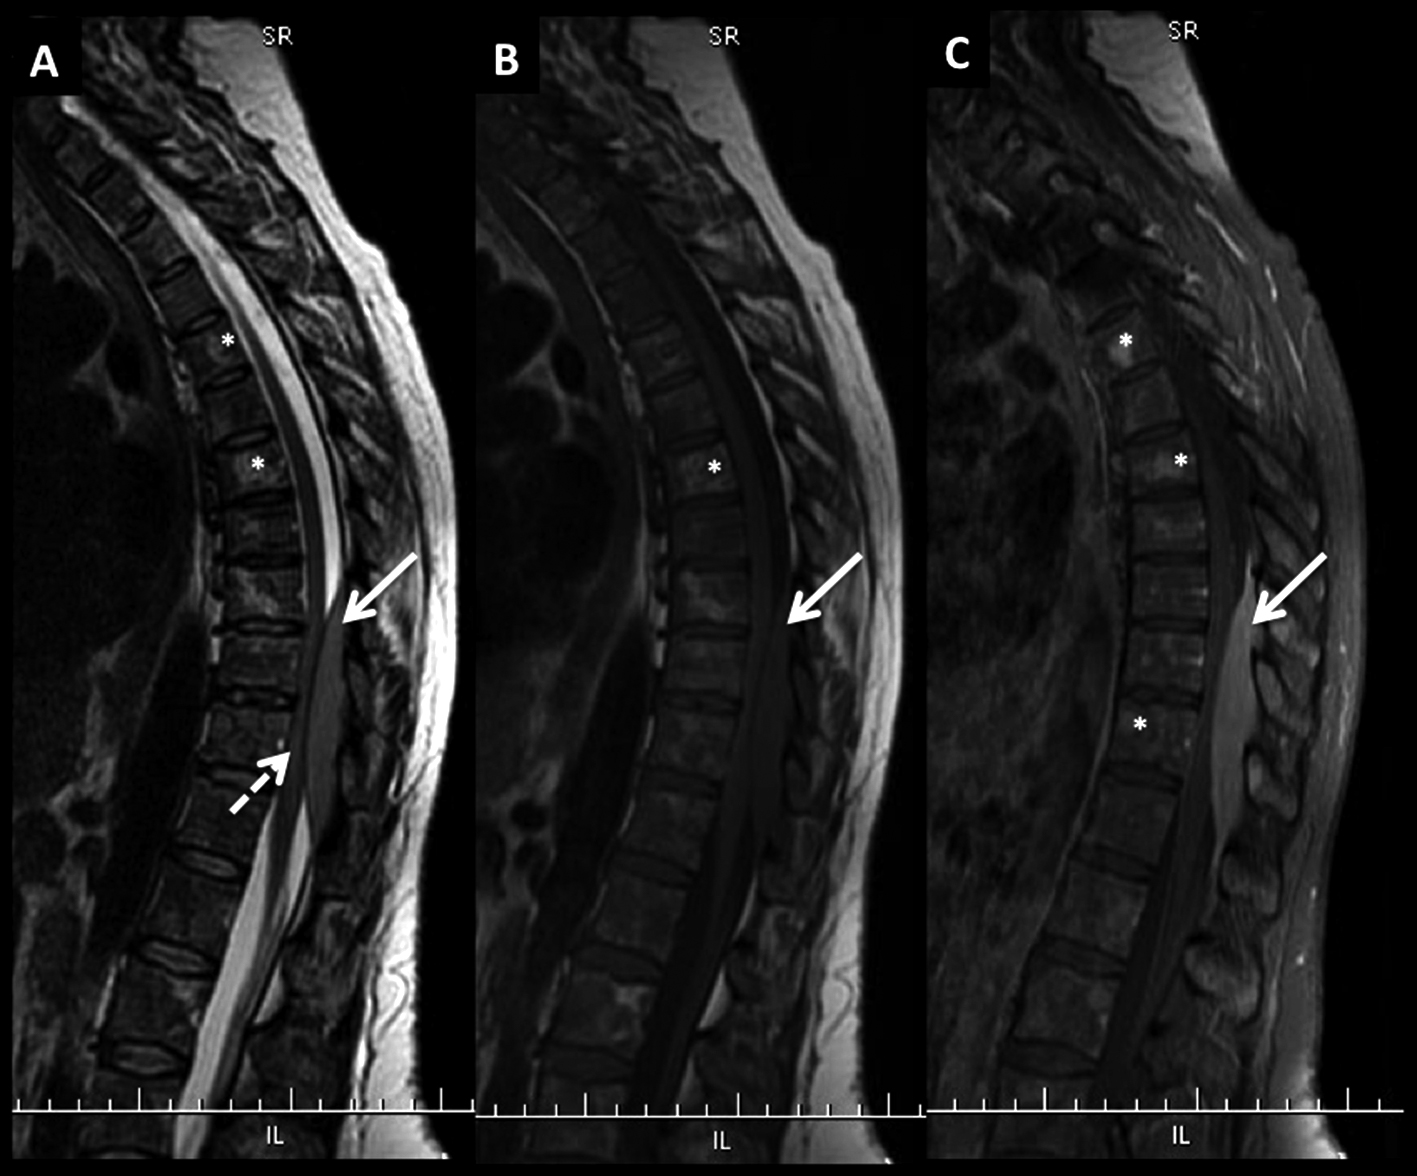

Paciente con diagnóstico de LNH sistémico y lesiones óseas múltiples (*) a nivel dorsal bajo y masa intrarraquídea extradural con compresión medular.

Las lesiones son de baja señal en T2 (A) y T1 (B) con edema óseo en STIR (C) y realce intenso, algo heterogéneo con el medio de contraste (D).

La masa intrarraquídea es sólida con intenso realce y que comprime el cordón medular. En secuencia T1 en fase (E) y fuera de fase (F) se observa el comportamiento habitual de las lesiones agresivas, con aumento de señal en el pasaje de una fase a la otra. En difusión b1000 (G) y mapa de ADC (H) las lesiones son de alta y baja señal respectivamente, un elemento habitual en lesiones agresivas.